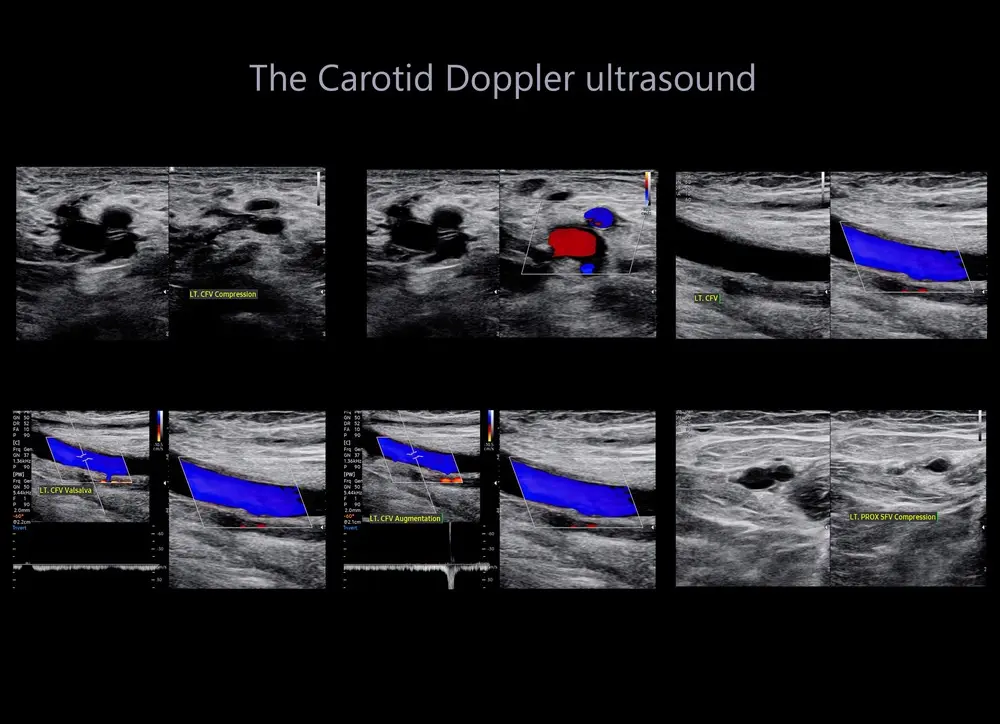

A carotid artery Doppler ultrasound is a non-invasive medical diagnostic imaging to check the circulation in the large arteries in the neck. This scan also looks at wall thickness of these arteries and if there are any clots/plaques. The narrowing of these arteries can be result in stroke hence this test plays a vital role in assessing the risk of stroke as the results of this test can help your healthcare professional to determine a treatment for lowering your stroke risk.

This scan includes the assessment of structures of common carotid arteries and its branches external carotid arteries and internal carotid arteries, and vertebral arteries.

The most common conditions of the carotid artery can be Carotid artery stenosis.